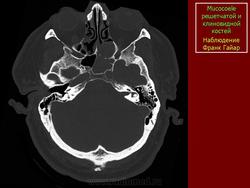

Мукоцеле

1.mu_.slayd364.jpg2.mu_.slayd365.jpg3.mu_.slayd366.jpg

3.c.slayd27.jpg4.c.slayd28.jpg